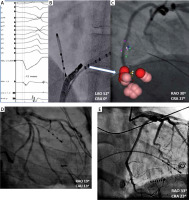

The 28-year-old female patient was admitted to our clinic with symptomatic, frequent, drug-refractory (β-blocker/propafenone) premature ventricular contraction (PVC) (Figure 1 A). Both echocardiography and cardiac magnetic resonance showed normal values of cardiac chamber size and function, without valvular dysfunction. Using an electroanatomical 3D system (Carto 3 UniVu) and ablation catheter (Thermocool SmartTouch) (Biosense Webster, Diamond Bar, CA, USA), activation maps of both the right and left ventricles and the coronary sinus (CS), respectively, were created. Despite delivery of radiofrequency (RF) energy with 30–40 W to the interventricular septum from the left and right side the ablation was unsuccessful. Thus, based on the local signals, fluoroscopy view and 3D map, RF energy application was performed within the coronary sinus in the proximity of the posterior cardiac vein (MCV) (Figures 1 A–C). In the 60th s of the successful RF application with 20 W, signs of ischemia were present in the 12-lead electrocardiogram. Urgent coronarography showed acute occlusion of the distal circumflex artery (LCx) (Figure 1 D). Successful wire crossing and recanalization were achieved with the coronary guide wire. Prolonged inflation with a 2.25 × 12 mm semi-compliant balloon demonstrated a suboptimal result and therefore a 2.5 × 15 mm sirolimus-eluting stent (Orsiro, Biotronic AG, Büllach, Switzerland) was implanted, with an optimal angiographic result (Figure 1 E). At discharge and in 6 months’ follow-up, there was no evidence of recurrence of ventricular extra beats in 24-hour Holter monitoring. Based on the medical history, physical examination and the results of the additional tests, no signs of coronary artery disease were found.

Figure 1

A – Recording of clinical arrhythmia, B, C – field of RF applications, D – occlusion of the distal LCx; decapolar catheter placed in CS, E – restored TIMI 3 flow in occluded artery